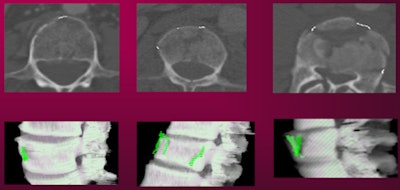

![]() |

| CAD-detected vertebral fractures shown on 2D (top row) and 3D views (bottom row). |